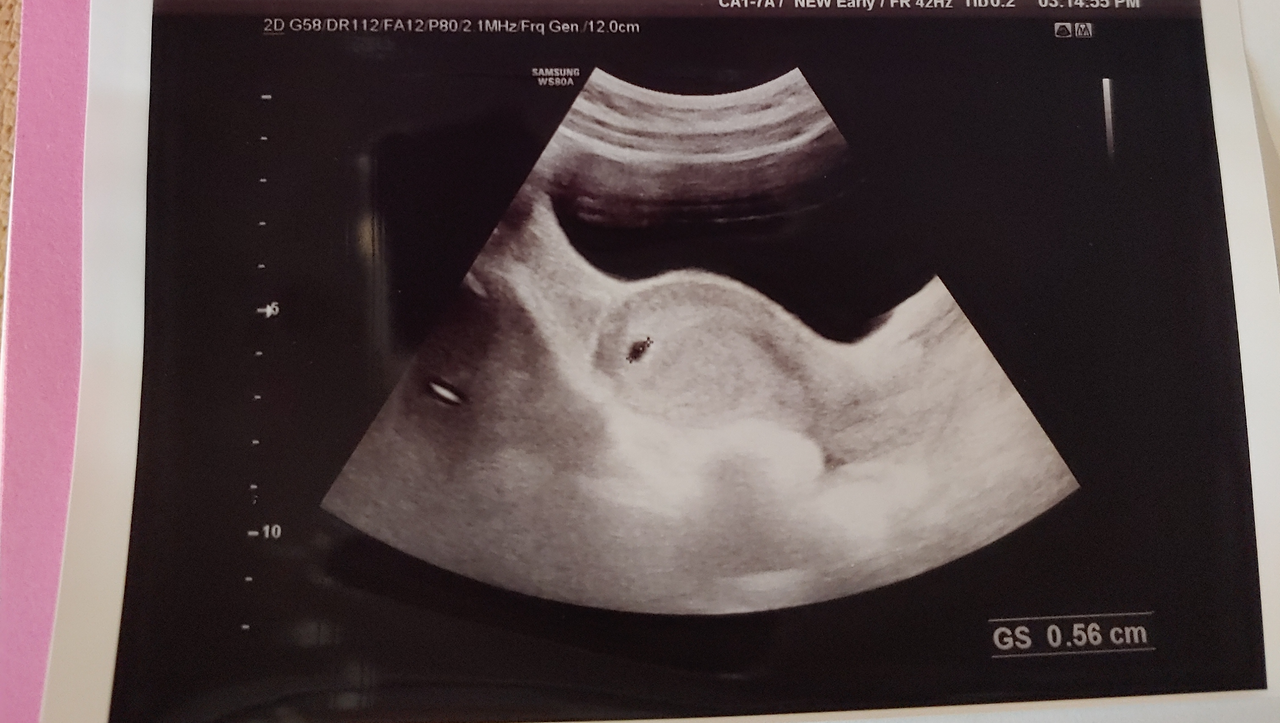

선생님이 초음파를 보기 시작했고, 뭔지도 잘 모르겠는 나의 자궁의 모습이 흑과 백으로 나누어져 보였다.

"아기집이 생겼네요. 5cm 정도고 다음 주 중에 오시면 심장소리도 들을 수수 있어요. 주수는 착상 일부터 기 때문에, 2주는 그냥 세고 들어가요. 지금 5주 정도 되셨네요."

"네..."

"엄마, 임신 초기에는 아랫배도 많이 당기고, 몸 온도도 올라가고 몸살감기 걸린 거 같은 거예요. 걱정하지 많고 많이 아프면 병원으로 오세요."

"오늘은 산모수첩 받아가시고, 임신증명서 뽑아드릴게요. 2 뒤에 봬요."